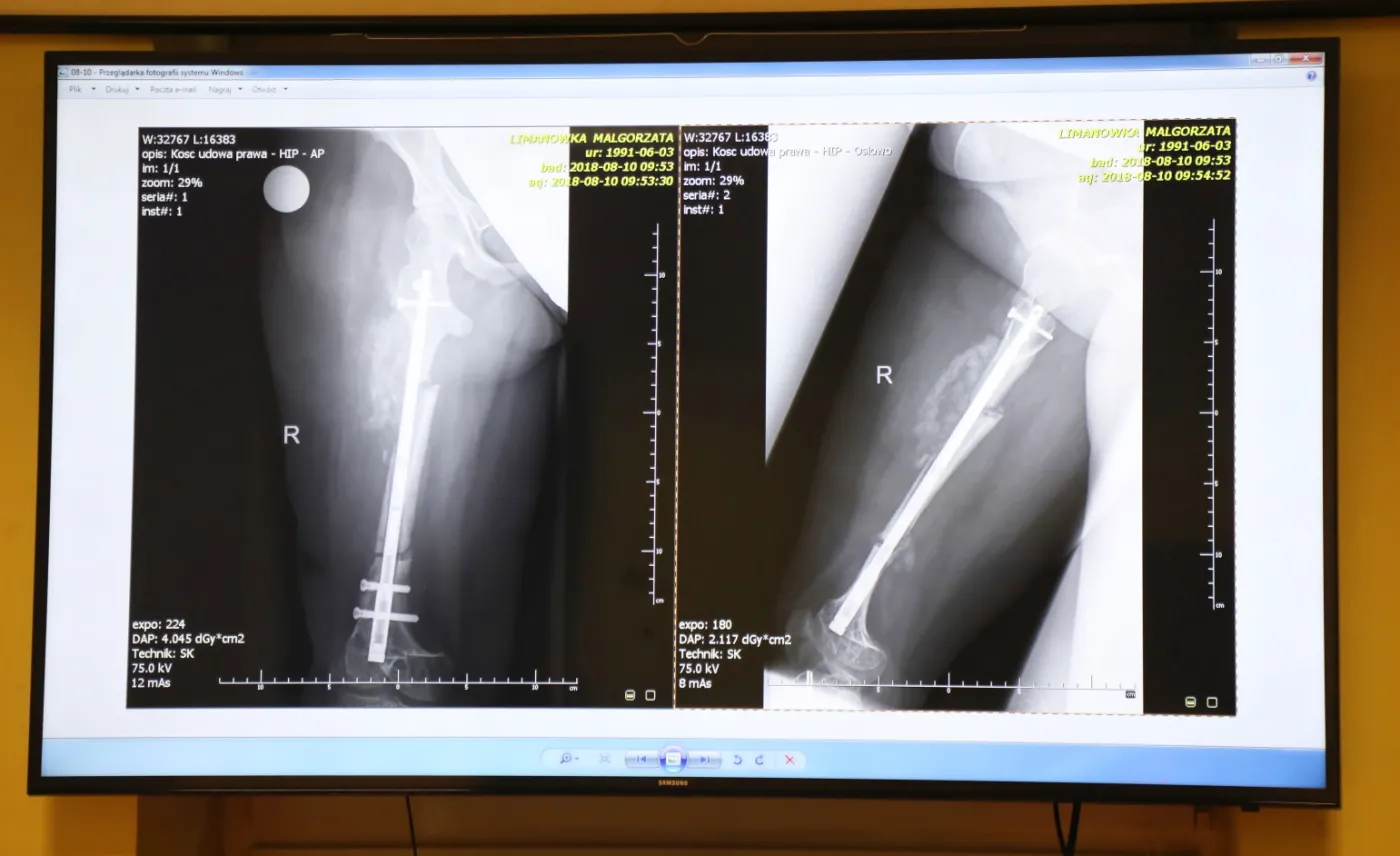

Pierwszą tego typu operację – wydłużenia kości za pomocą pola magnetycznego – przeprowadzono w Szpitalu Specjalistycznym imienia Stefana Żeromskiego w Krakowie. 27-letniej pacjentce cierpiącej na wrodzoną łamliwość kości wszczepiono w kość udową specjalny gwóźdź sprowadzony z USA, przez który przepuszczano pole i stymulowano tym samym kość do wzrostu. Od lipca, kiedy kobieta przeszła operację, do 18 września, kiedy lekarze pochwalili się jej wynikami, udało się wydłużyć kość o 3 centymetry.

2/6INNOWACYJNA OPERACJA WYDŁUŻENIA KOŚCI